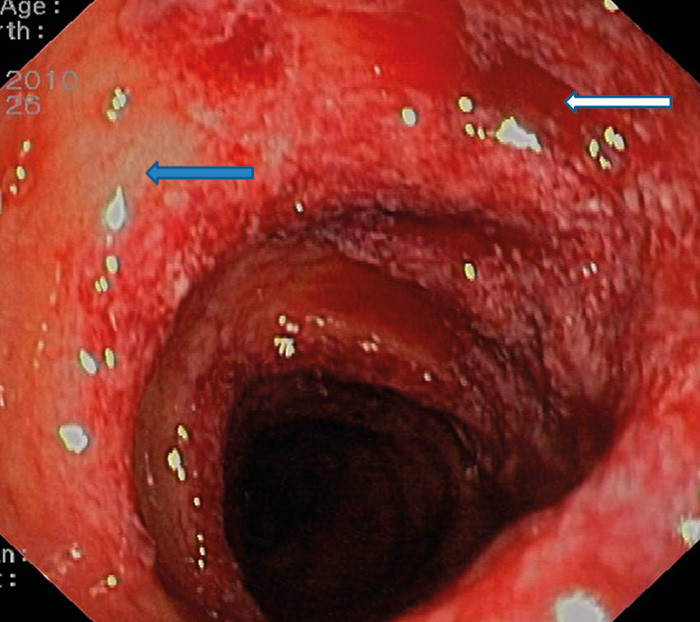

Opplysningen om friskt blod i avføringen førte til at man valgte å gjøre CT colon på mistanke om kolitt. CT colon viste en uspesifikk veggfortykkelse i venstre del av colon. Røntgen av tynntarm påviste verken kalibervekslinger, fortykket vegg eller stenoser. Ved koloskopi fant man forandringer med flekkvis rubor, ødem og submukosale blødninger i colon sigmoideum og colon descendens opp til venstre fleksur (fig 1). Histologi av tykktarmslimhinnen viste løsnet overflateepitel, fravær av krypter i tillegg til atrofi og ødem (fig 2).

Det histologiske funnet passet ikke med inflammatorisk tarmsykdom, men var typisk for iskemisk kolitt. Samlet passet dette best med iskemisk skade av tarmen.